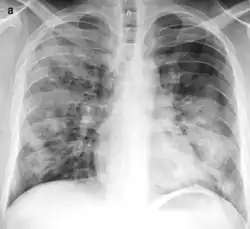

![]() | |

| Typical distribution of lobar pneumonia (left in image) and bronchopneumonia (right in image) | |